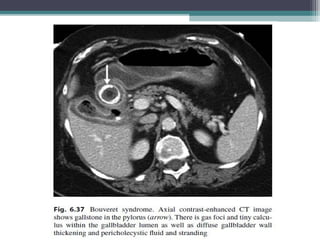

 BOUVERET SYNDROME : Gastric outlet obstruction due to gall stones impacted

in the distal stomach or proximal duodenum

GALL STONE ILEUS •Its associated with Cholecytsoduodenal fistula • The gall stone passes into the duodenum by eroding the inflamed gall bladder wall and leads to small bowel obstruction • Clinical symptoms : RIGLERS TRIAD  Pneumobilia  Small bowel obstruction  Ectopic gall stone usually in right iliac fossa  Gas in biliary tree can be recognised by its branching pattern with gas being more prominent centrally  Gas in portal vein tends to be peripherally located in small veins around the edge of the liver  BOUVERET SYNDROME : Gastric outlet obstruction due to gall stones impacted in the distal stomach or proximal duodenum